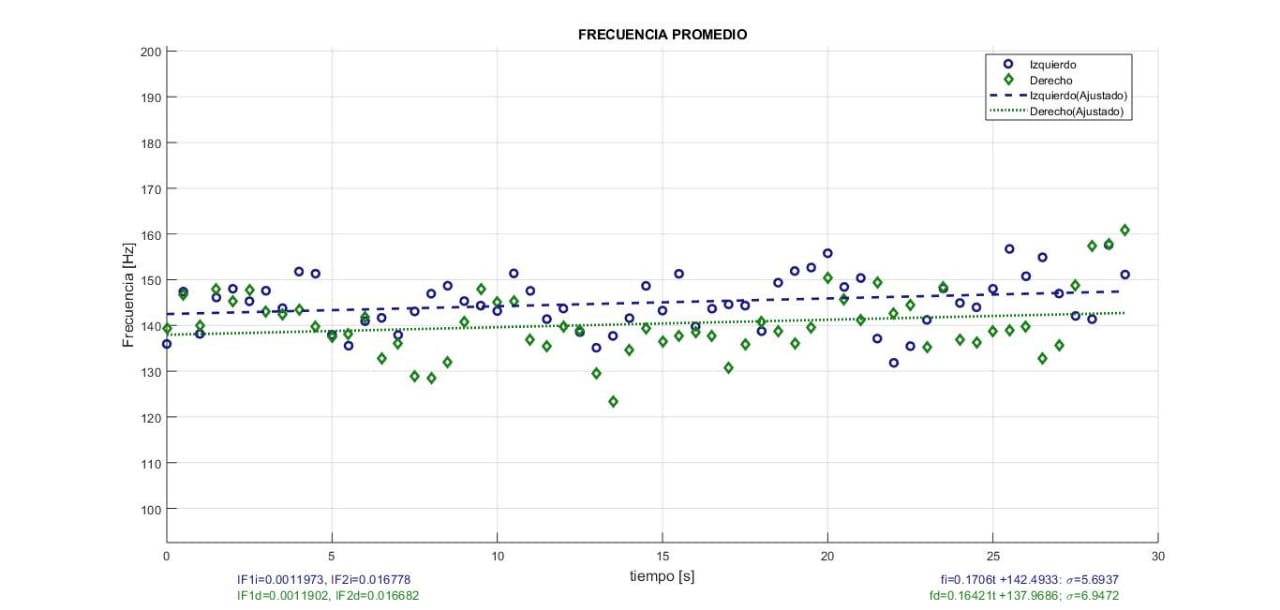

Valor de la frecuencia promedio MNF (Mean Frequency) de señal EMGS cruda registrada durante contracción isométrica en oclusión centrica (OC), (Laboratorio de fisiología oral, 2019)

La repetibilidad de las variables extraídas de la señal EMGS basadas en la estimación de la amplitud y la densidad de la potencia espectral, como RMS, ARV, MNF y MDF, mejora si se utiliza una metodología de estandarización y normalización como la sugerida por [26-30]. Sin embargo, no siempre es viable.